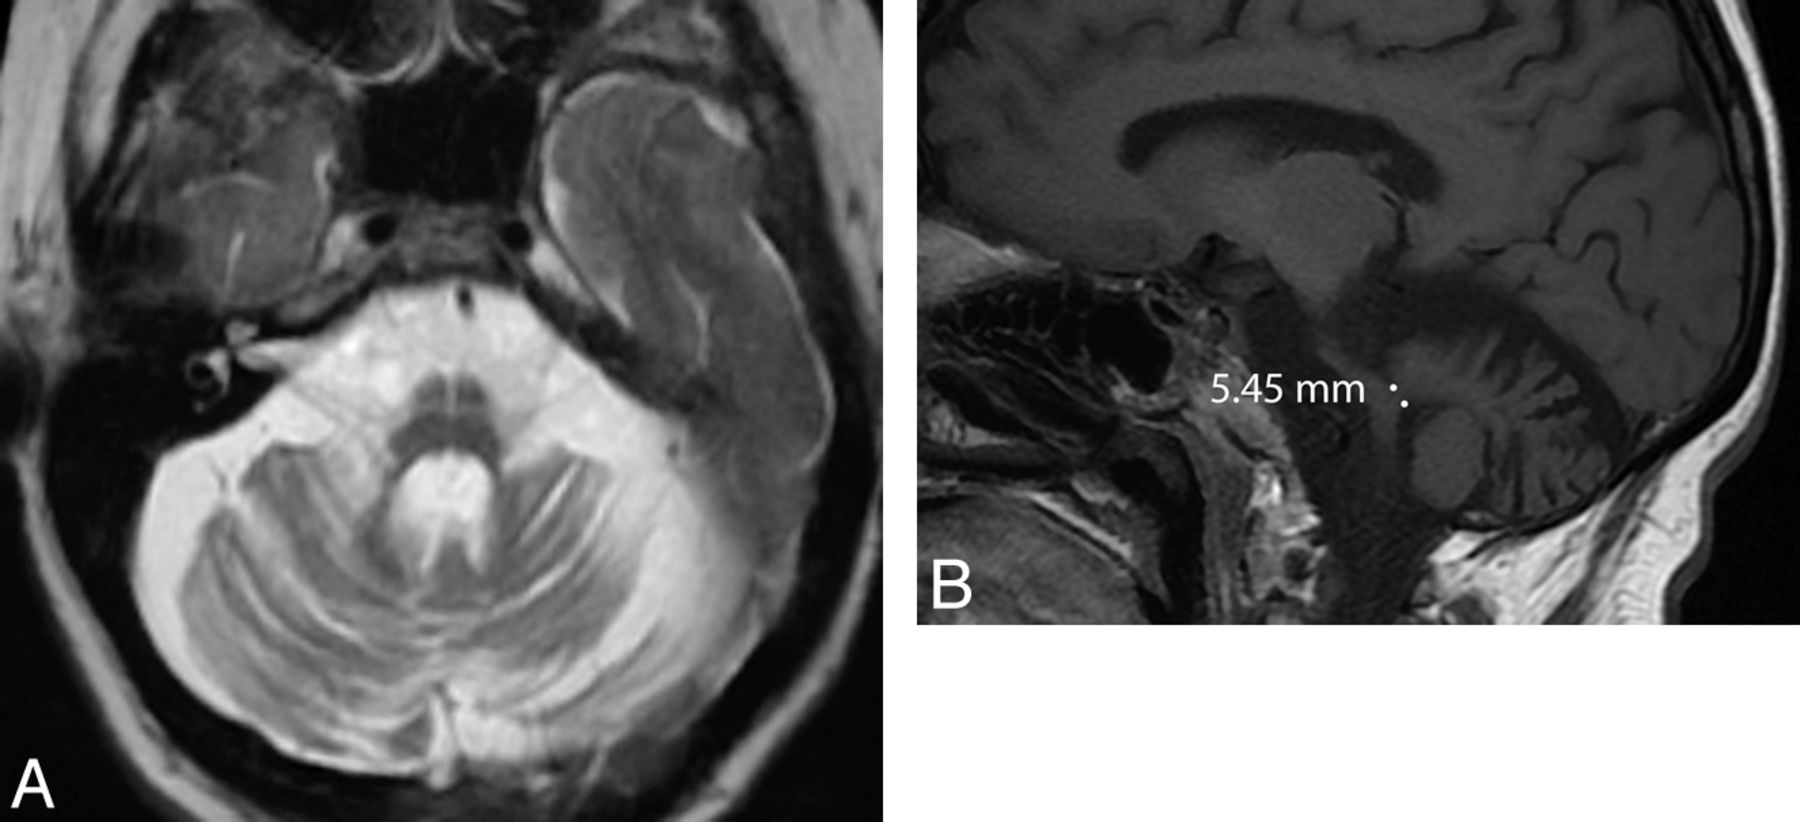

PSP accounts for a small minority of patients with parkinsonism. Neuropathologically, this tauopathy is characterized by neuronal degeneration of the nigrostriatal pathway, basal ganglia, and brain stem nuclei with deposition of neurofibrillary tangles. A number of MR imaging features suggestive of PSP have been described, such as dilation of the third ventricle and signal increase of the midbrain.5,26 Although often absent, atrophy of the red nucleus, frontal and temporal lobe, and an anteroposterior midbrain diameter of <17 mm can each differentiate PSP from MSA with at least 75% positive predictive value (Fig 4). If one uses a “MR parkinsonism index” [(pons/midbrain) · (middle cerebellar peduncle/superior cerebellar peduncle)], PSP can be prospectively distinguished from idiopathic Parkinson disease, MSA-P, and controls with 100% positive predictive value.27 Group studies additionally demonstrate that atrophy in the striatum and frontotemporal cortices, measured with volumetry and voxel-based morphometry, respectively, differentiate those with PSP from controls.9,28 Additionally, white matter atrophy in the subthalamic region can distinguish PSP from controls and idiopathic Parkinson disease when using voxel-based morphometry.29

Axial T2-weighted MR imaging sequence in a patient with PSP (A) demonstrating increased midbrain signal intensity (which is only 60% sensitive and 70% specific compared with MSA) and an atrophic midbrain with an anteroposterior diameter of <17 mm (which is 23% sensitive and 96% specific compared with MSA).5 The signs are nonspecific in the wider population—for example, midbrain signal intensity can be seen in Wilson disease and a severely atrophic midbrain can be seen in CBD. The concave posterolateral borders of the atrophic midbrain give it a “morning glory” flower appearance. The corresponding sagittal T1-weighted sequence (B) shows tectal atrophy with a “hummingbird” appearance.